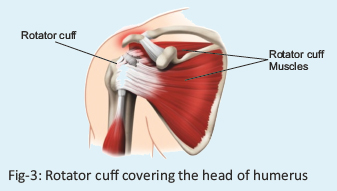

Musculotendinous (Rotator) Cuff